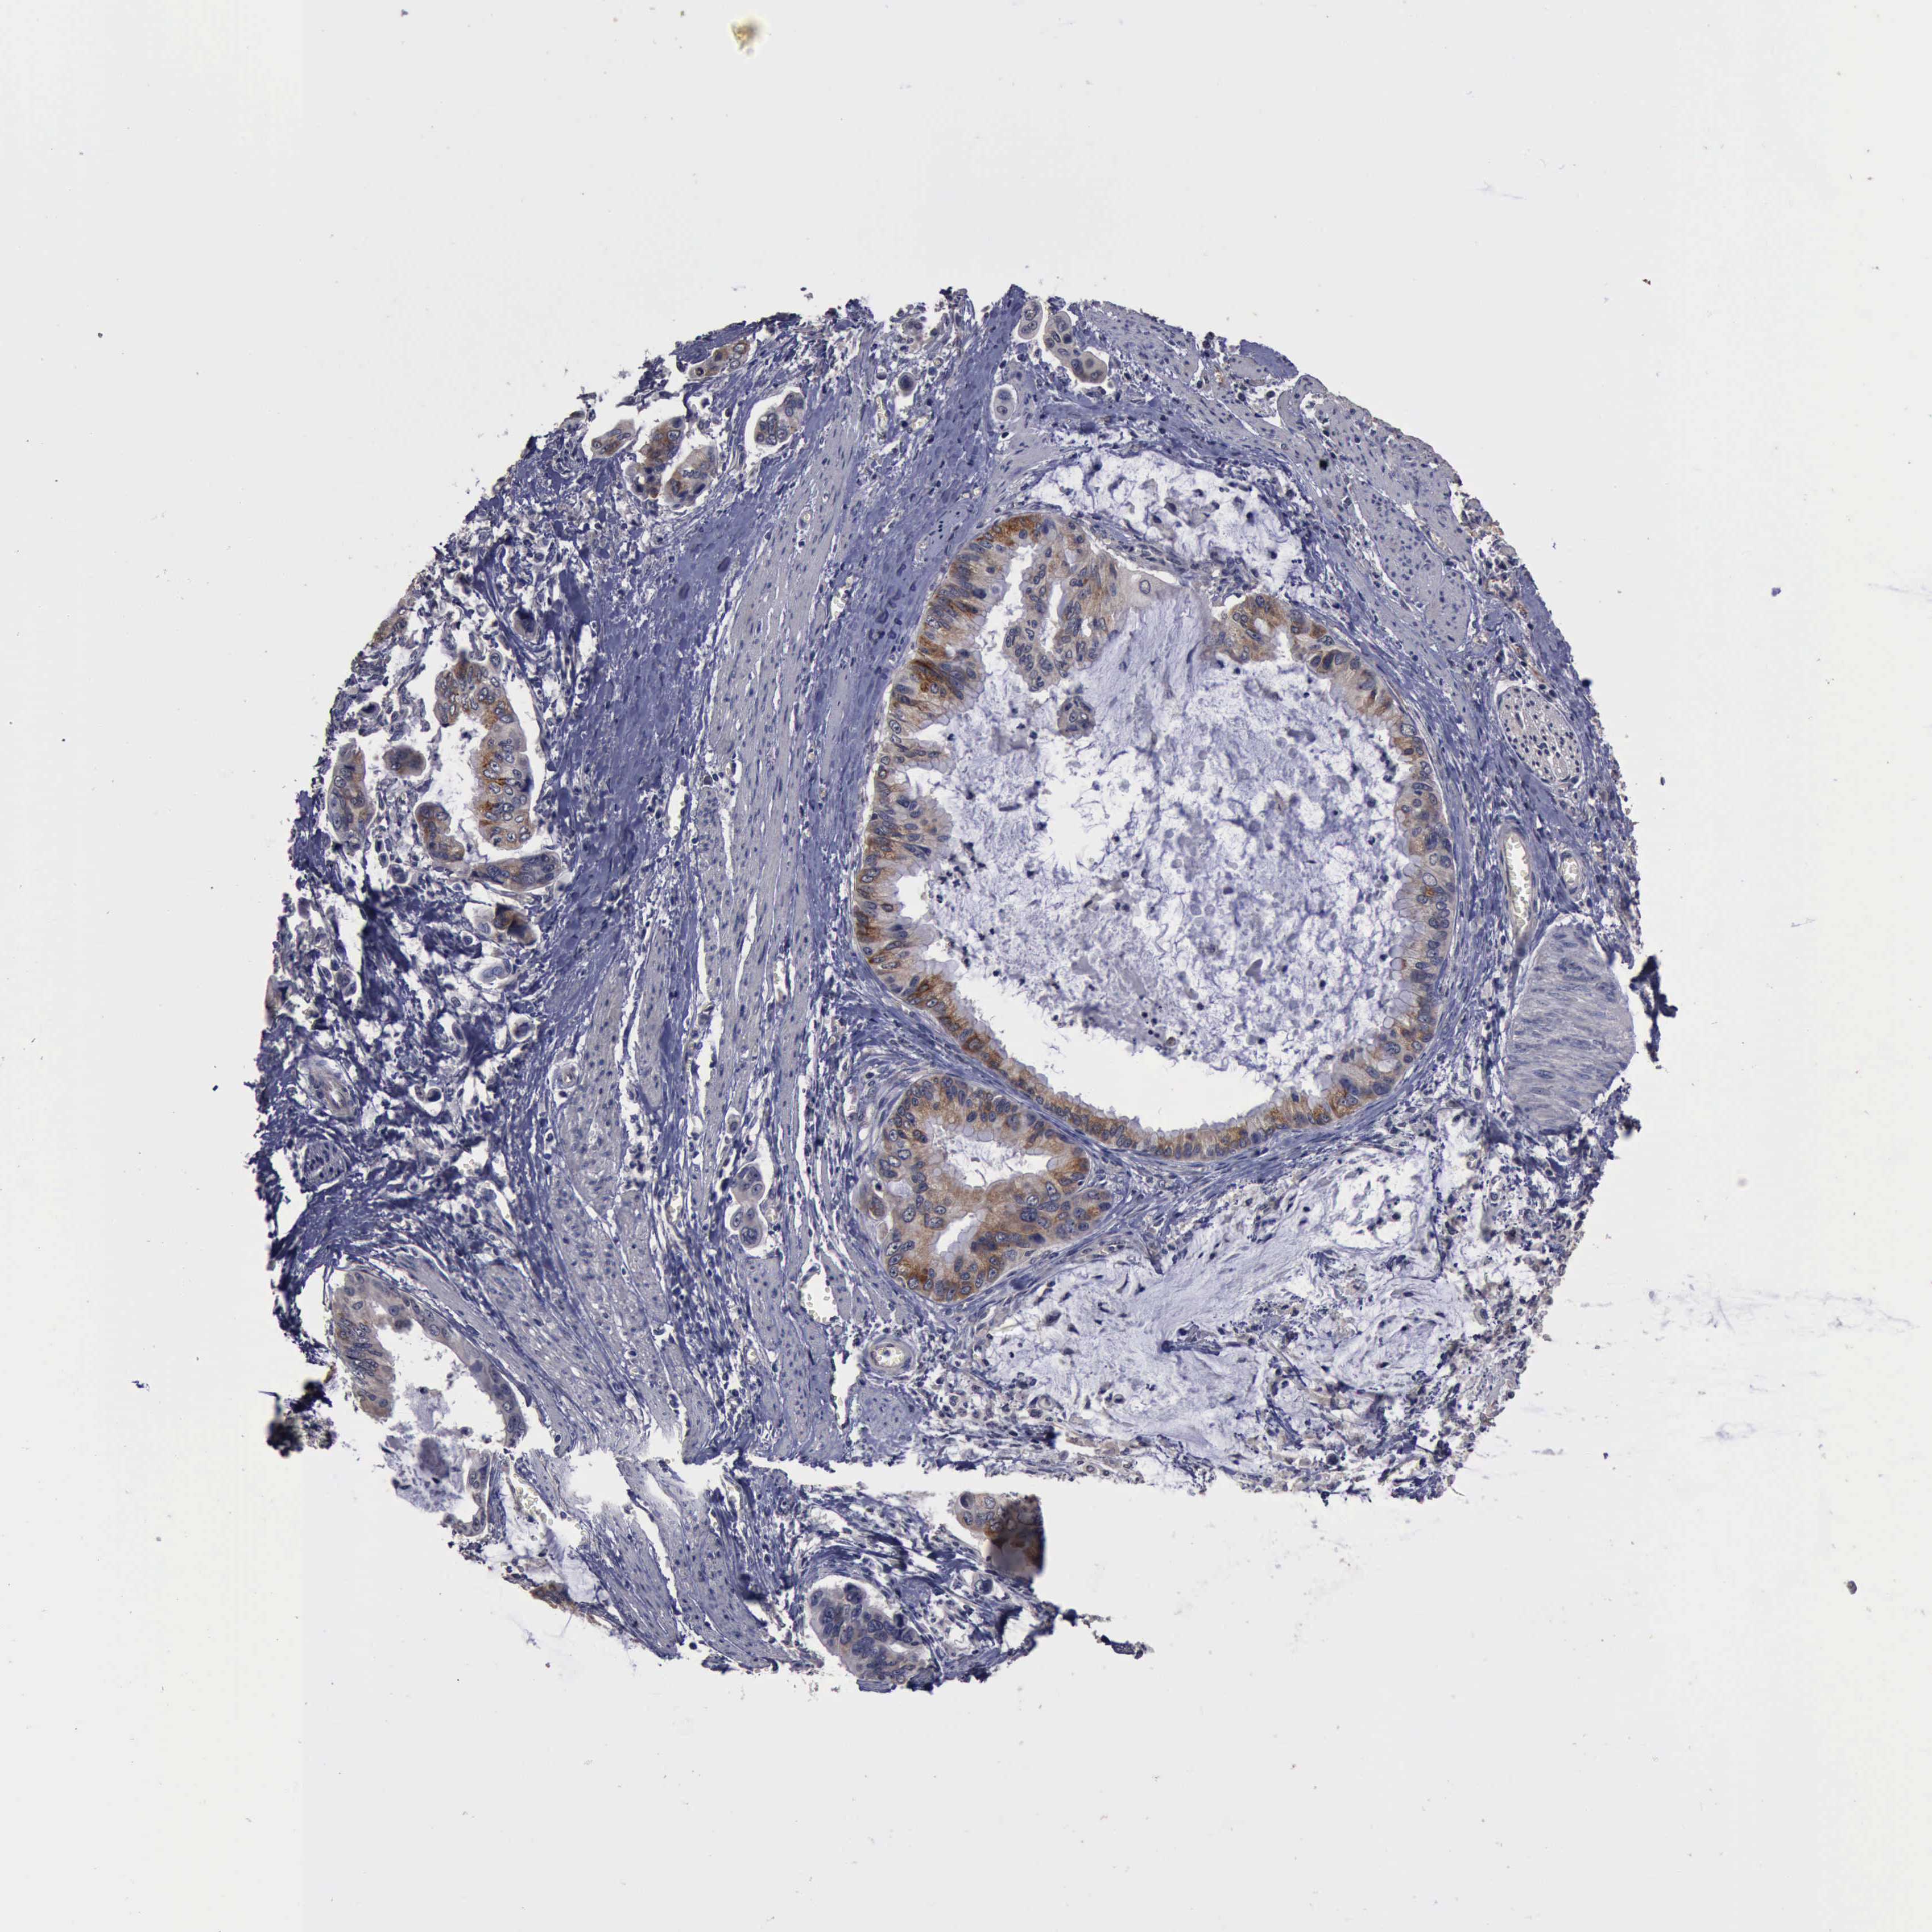

STOMACH CANCER - Protein expressioni

A mouse-over function shows sample information and annotation data. Click on an image to view it in a full screen mode. Samples can be filtered based on level of antibody staining by selecting one or several of the following categories: high, medium, low and not detected. The assay and annotation is described here.

Note that samples used for immunohistochemistry by the Human Protein Atlas do not correspond to samples in the TCGA dataset.

Antibody stainingi

Antibody staining in the annotated cell types in the current human tissue is reported as not detected, low, medium, or high, based on conventional immunohistochemistry profiling in selected tissues. This score is based on the combination of the staining intensity and fraction of stained cells.

Each image is clickable and will lead to virtual microscopy that enables deeper exploration of all samples and also displays staining intensity scores, fraction scores and subcellular localization as well as patient and tissue information for each sample.

Antibody HPA001100

Staining

High

Medium

Low

Not detected

Intensity

Strong

Moderate

Weak

Negative

Quantity

>75%

75%-25%

<25%

None

Location

Nuclear

Cytoplasmic/membranous

Cytoplasmic/membranous,nuclear

Adenocarcinoma, NOS